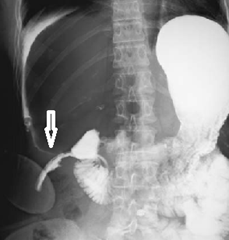

This is radiology images of Duodenal perforation (arrow) detected 2 days after laparoscopic cholecystectomy. A water-soluble contrast agent was used to perform this study.